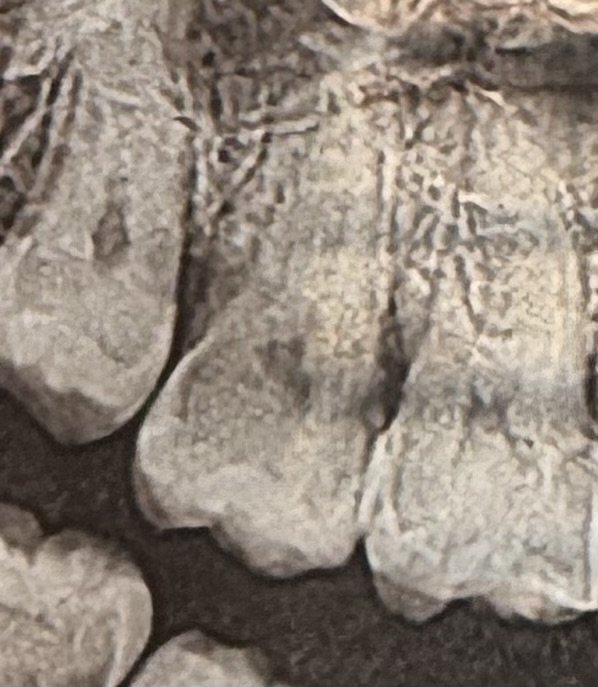

Как се премахва зъбният камък и боли ли?

Процедурата за отстраняване на зъбен камък е безболезнена, ако се извърши внимателно. Ултразвуковият апарат произвежда хиляди трептения в секунда, които разхлабват и премахват плаката от повърхността на зъба. След почистване може да има леко дразнене на венците, но то отшумява до следващия ден. Редовното почистване на зъбния камък е важно, тъй като натрупването му може да доведе до пародонтоза.